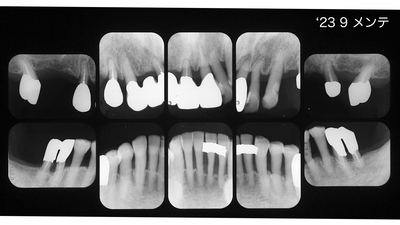

初診時30代男性。「歯並びを治したい」が主訴でしたがプロービングデプス全顎8〜9mmの重度歯周炎でした。歯周治療後全顎pd2~3mmに改善を確認、矯正治療は専門医山田秀樹先生にお願いしました。

矯正治療が終わりました、といわれても上顎犬歯遠心にスペースを残す、やや控えめな歯牙移動、、、それが私の眼には物足りなく思ったものでした。しかし経過を観察すること初診から5年、骨レベルは安定し歯肉はタイトに引き締まってプローブははいらないばかりか付着歯肉が増大してきました。良好な経過から矯正専門医の適切で妥当な判断だったといえます。さすがです。

メンテナンスに移行

急発〜挺出〜咬合性外傷 で上顎前歯は抜けそうでしたが、なんとか助かりました。右上1右下2近心のX-P像に注目ください。動的治療期間2年弱ですからまあまあでしょう。